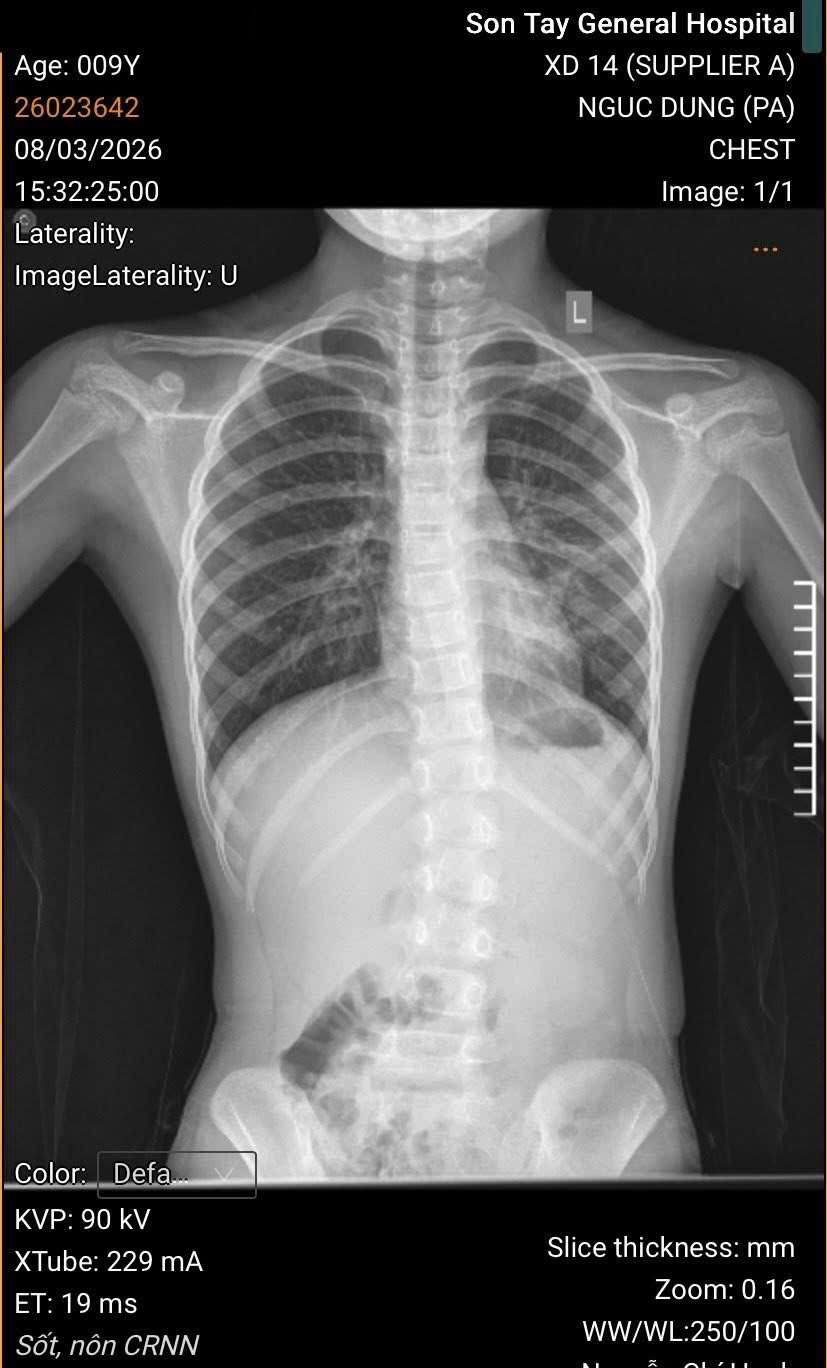

🧬🧬Người bệnh là cháu TRỊNH MINH H – 9 tuổi. Địa chỉ Phường Sơn Tây – Hà Nội.

⏰Ngày 08/03/2026 Đến Bệnh viện đa khoa Sơn Tây khám vì ho nhiều, lâu ngày không khỏi. Trong quá trình điều trị cho cháu H ngoài viêm phế quản, bác sĩ khoa Nhi – bệnh viện đa khoa Sơn Tây còn đánh giá phát hiện bé bị CONG VẸO CỘT SỐNG mà trước đó gia đình không hề biết. Cháu H cảm thấy bị đau mỏi lưng liên tục, dáng đi không cân bằng.

🩻🩻 Chụp xquang, dựng hình cột sống và đo chỉ số Scobb thấy tình trạng cong vẹo còn khả năng tập phục hồi chức năng được, chưa cần thiết can thiệp ngoại khoa. Khoa Nhi đã hội chẩn liên khoa với khoa Phục Hồi Chức Năng lên phương án hỗ trợ điều trị.